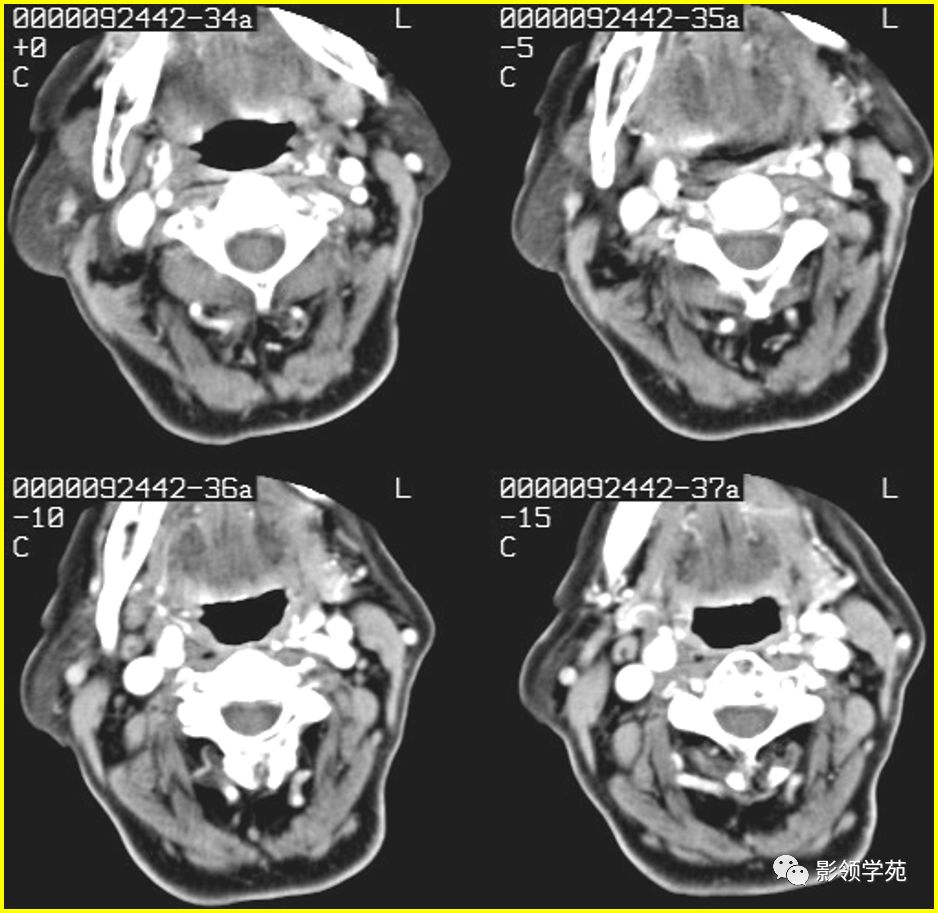

读片:腮腺ct平扫病例